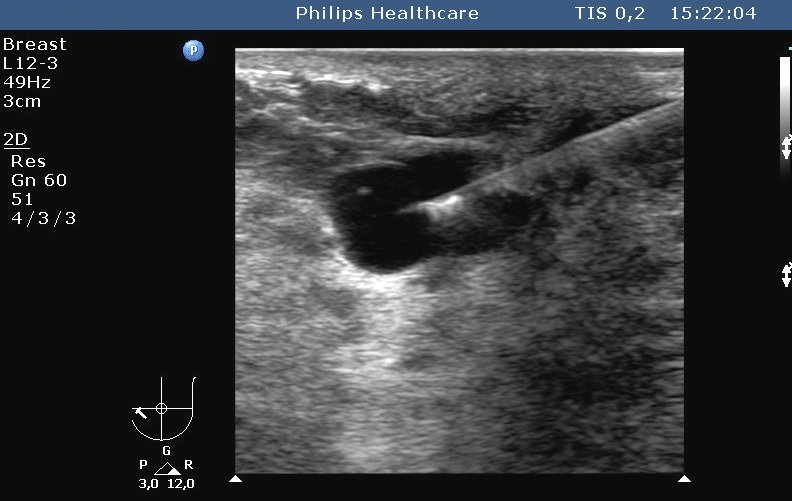

Nowadays it is the most commonly used method. Both superficial (figure 3.) and deep (figure 4.) lesions can be biopsied.

Image

Figure 3. – US guided, fine needle aspiration biopsy (breast cyst puncture)